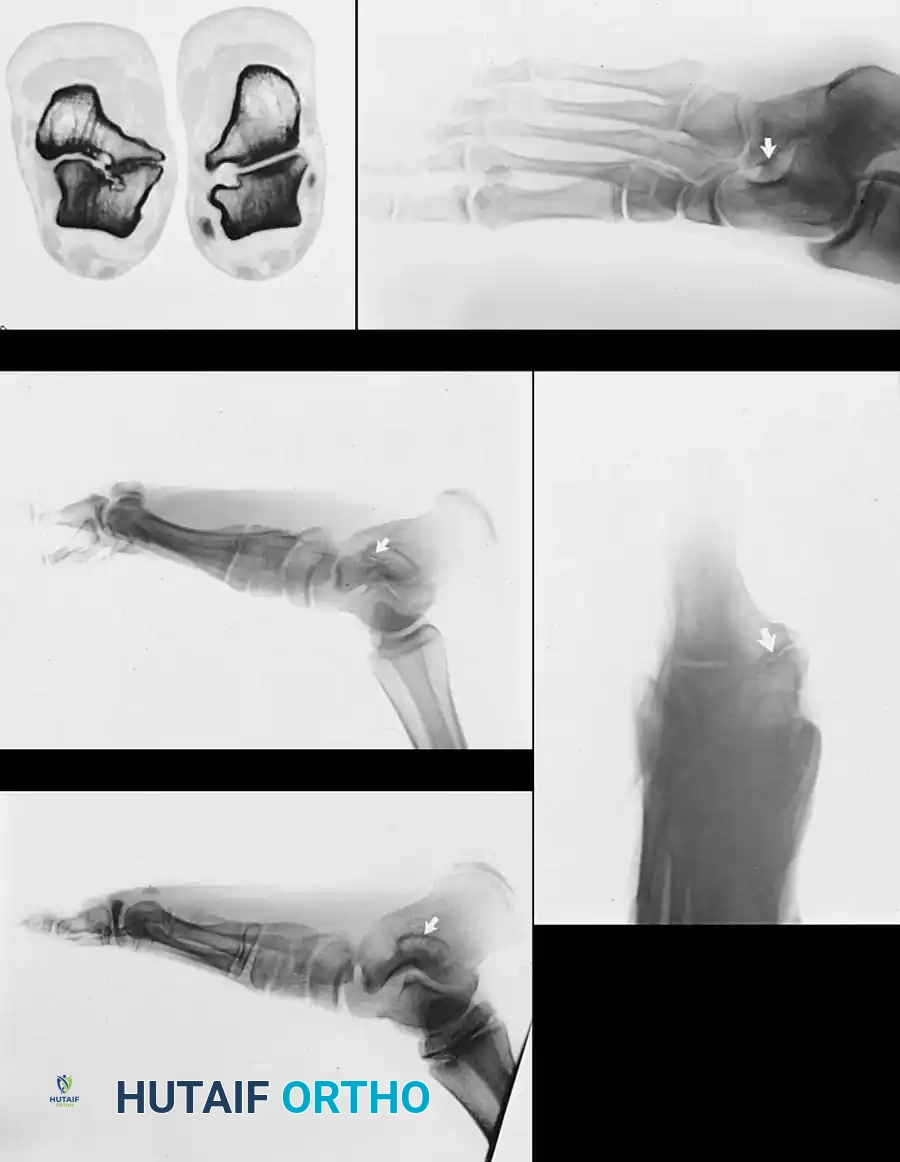

التصوير الطبي هو الحجر الأساس لتأكيد التشخيص وتحديد نوع وموقع المشكلة بدقة:

- الأشعة السينية (X-rays):

- للتشخيص المبدئي، يتم التقاط صور بوضعيات خاصة.

- لتشخيص التحام العقب والزورقي، تعتبر الصورة المائلة بزاوية 45 درجة هي الأفضل.

- لتشخيص التحام الكاحل والعقب، يتم استخدام وضعية خاصة تسمى (Harris-Beath view) لتصوير المفصل الأوسط.

- الأشعة المقطعية (CT Scan): تعتبر المعيار الذهبي لتشخيص التحام الكاحل والعقب. توفر صوراً ثلاثية الأبعاد ومقاطع عرضية دقيقة توضح حجم الالتحام، موقعه، وحالة المفاصل المجاورة، مما يساعد الجراح في التخطيط للعملية.

- الرنين المغناطيسي (MRI): قد يستخدم في بعض الحالات لتشخيص الالتحامات الليفية أو الغضروفية التي قد لا تظهر بوضوح في الأشعة السينية أو المقطعية.